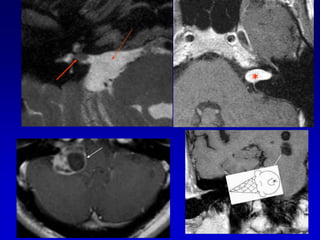

GLOMUS YUGULAR(paraganglioma)Erosion de la espina yugularInvasion hacia la caja timpánica

Caso 2TAC-RM

Caso 3TAC RM ANGIO

Caso 3

postembolizacion

Glomus timpánico